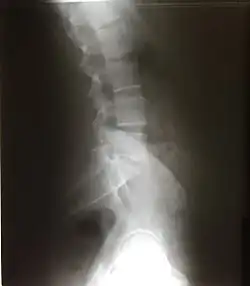

Поясничный отдел

В поясничном отделе располагается 5 позвонков. На поясничный отдел приходится очень большая масса, поэтому тела поясничных позвонков самые крупные. Остистые отростки направлены прямо назад. Суставные отростки обращены сагиттально. Есть рёберные отростки (рудименты рёбер), добавочные отростки (остатки поперечных отростков, не слившиеся с ребром), сосцевидные отростки — след прикрепления мышц.